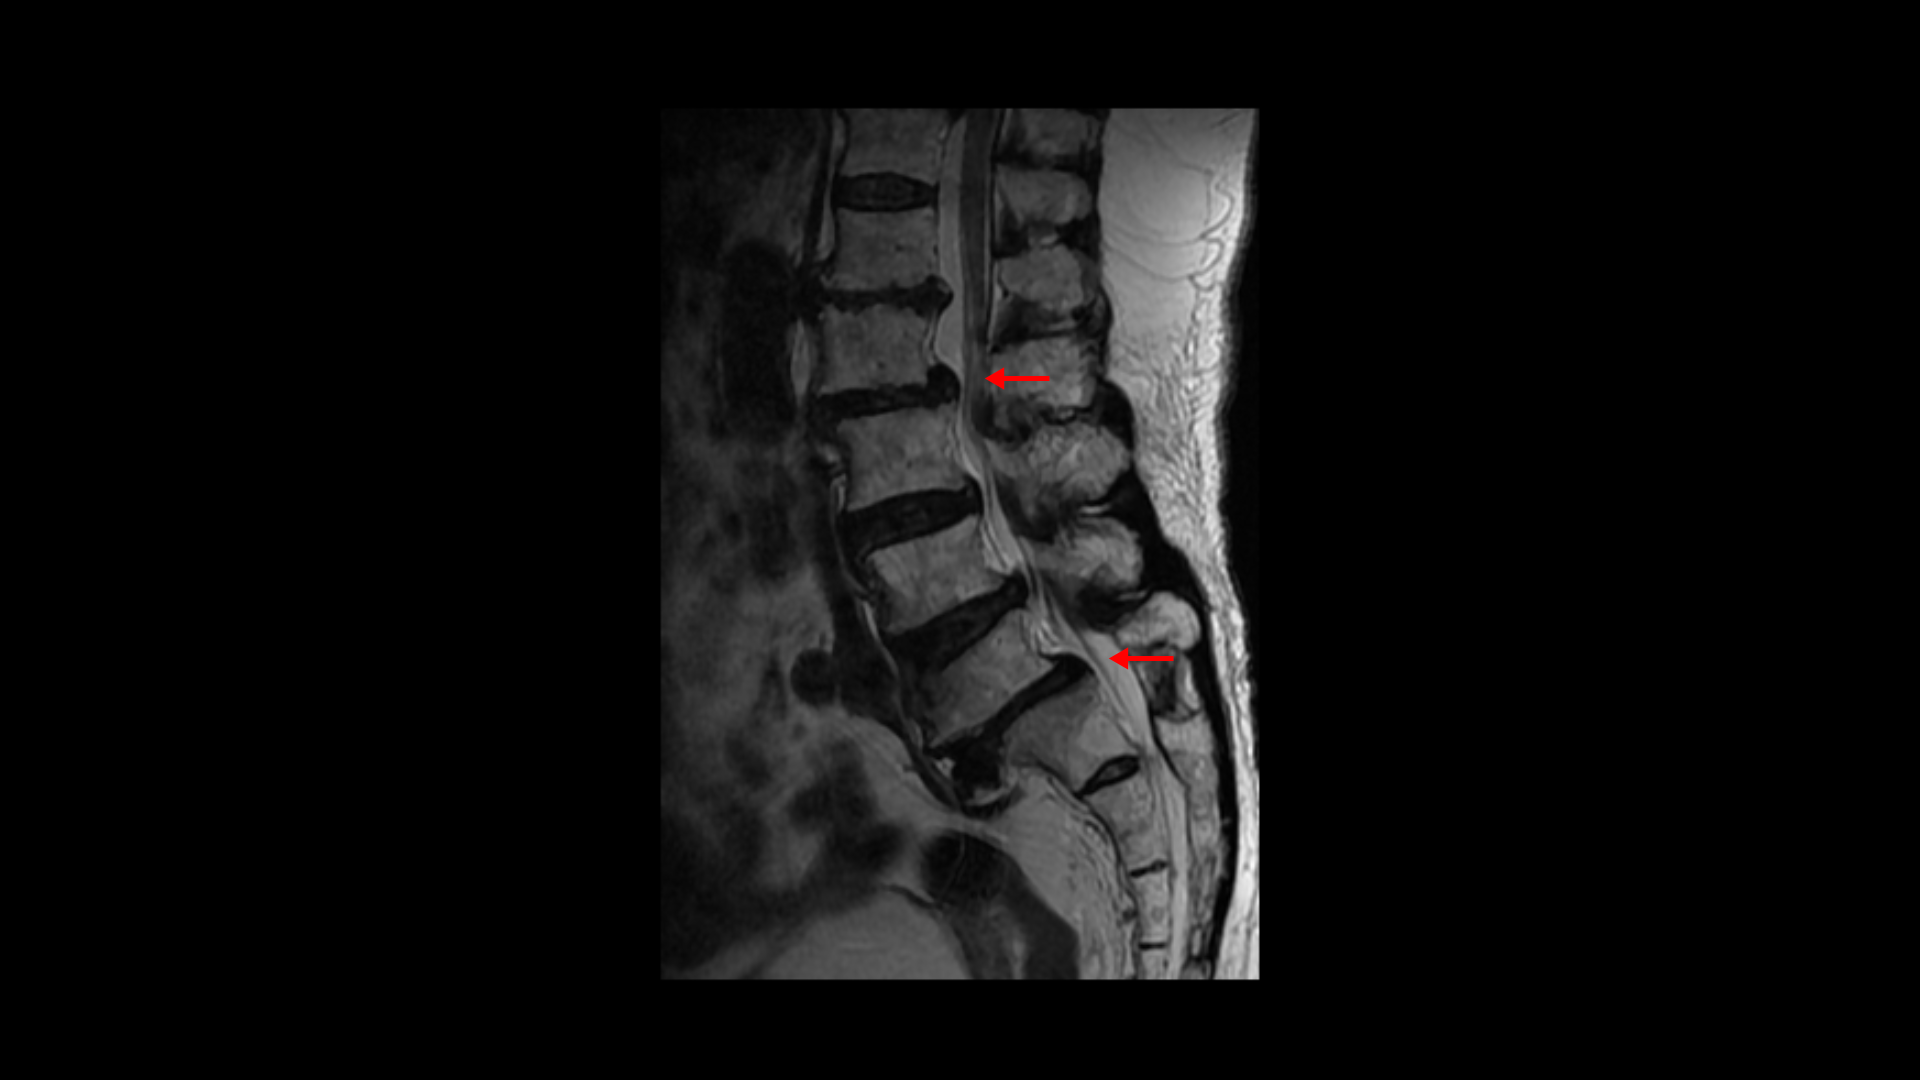

이분 MRI를 보면 보시다시피 허리의 5마디가 전부 퇴행이 진행되어 있습니다.

우선 전방전위가 2마디에 있고

여러 마디 2번 3번, 4번 5번에 척추관협착이 있고

2번 3번, 4번 5번, 오른쪽 신경가지가 빠져나가는 구멍들이 다섯 마디 전부가 다 오른쪽 좁아져 있습니다.

이분의 오른쪽 엉치와 다리가 저리고 아픈 원인은 이것 때문인 걸로 보입니다.